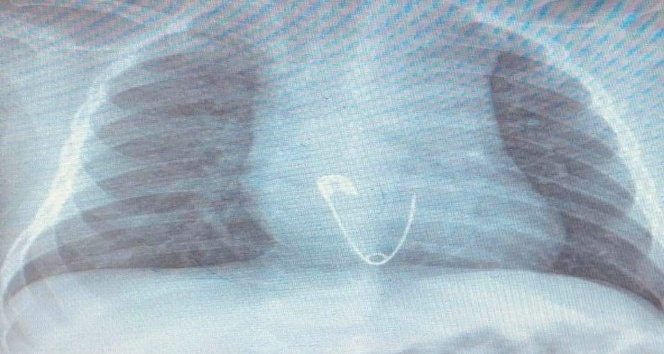

Hastanın Diyarbakır’dan Elazığ’a geldiğini belirten Prof. Dr. Yaşar Doğan, “Hastayı kabul ettik, 5 aylık bir hasta. Bize gelmeden önce üzerinde bulunan nazar boncuğunu çengelli iğne ile birlikte ağzına götürmüş. Aile de fark edince müdahale etmiş, ağzındaki nazar boncuğunu çıkarmış fakat o esnada çengelli iğne yemek borusuna kaçmış. Hasta geldiği zaman çektiğimiz röntgende çengelli iğne yemek borusunun alt kısmında takılı vaziyetteydi. Hastaya 15 dakikalık sedasyon altında işlem yapıldı, endoskopi ile parça çıkarıldı. Hasta şu anda gayet iyi. Biraz sonra da evlerine göndereceğiz” dedi.